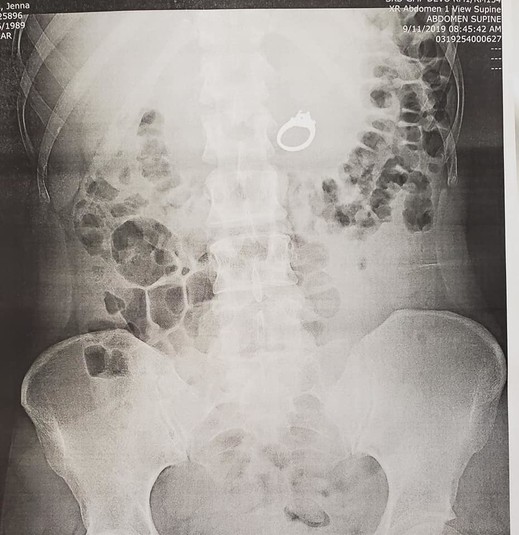

Рентген показал, что кольцо с бриллиантом в 2,4 карата действительно находится в ее желудке. Врачи решили, что неразумно ждать, пока кольцо выйдет естественным путем, и назначили операцию. Она прошла успешно.